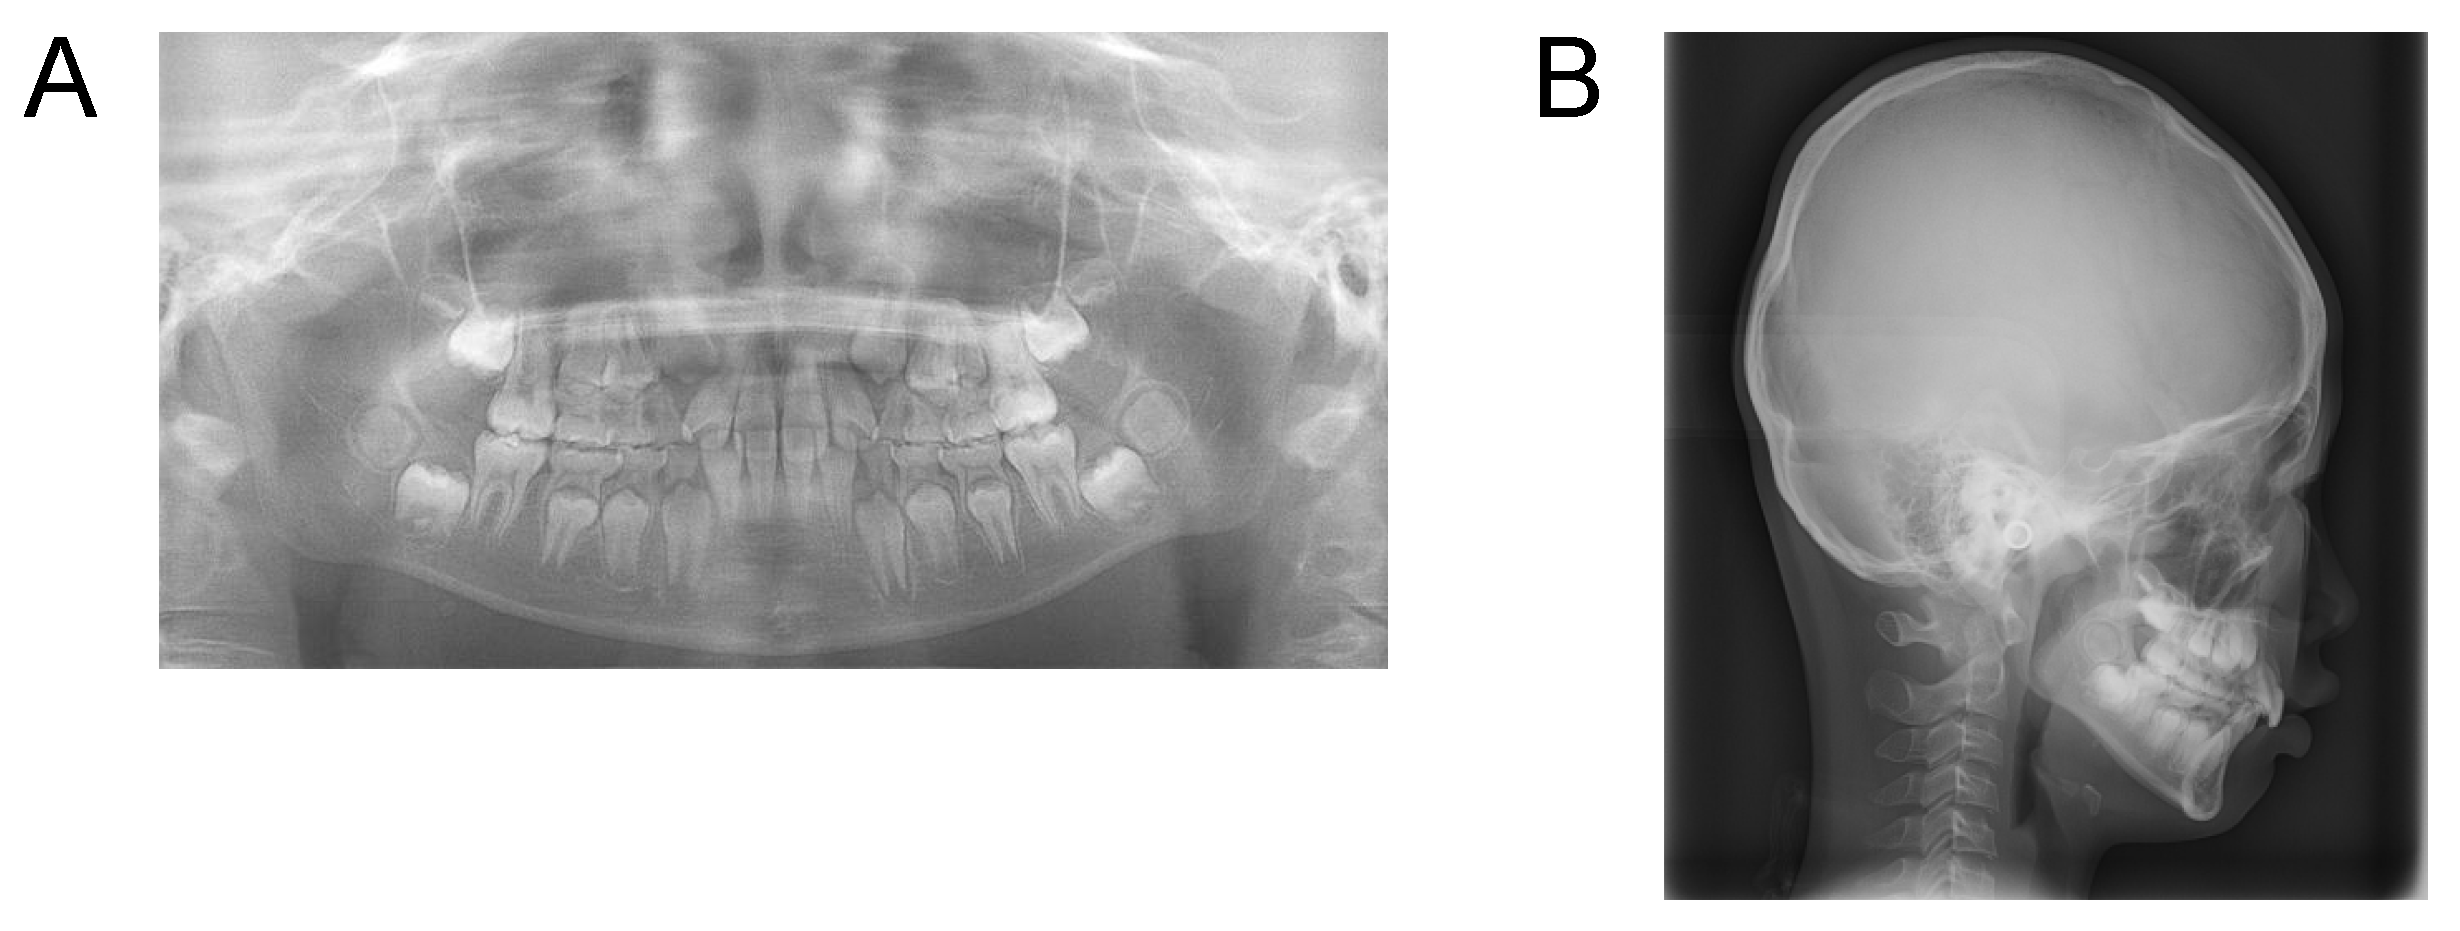

Case 3. Findings from initial examination